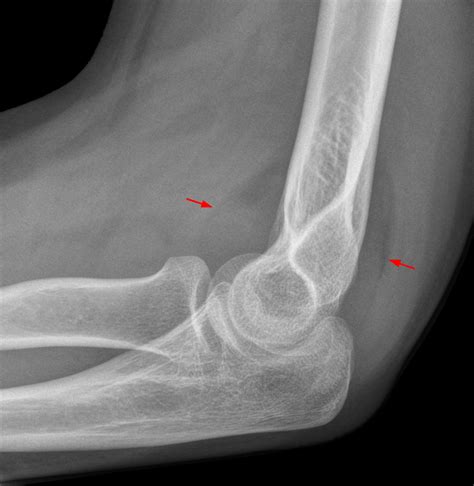

Diagnosing issues related to the elbow fat pad typically involves a combination of physical examination and imaging tests. Your healthcare provider may perform the following:

• Imaging Tests: X-rays, ultrasound, or MRI scans can provide detailed images of the elbow joint and surrounding tissues, helping to identify any abnormalities or injuries.

• elbow fat pads x ray

• positive posterior fat pad sign

• positive fat pad sign elbow

• elbow fracture fat pad sign

• elbow elevated fat pad